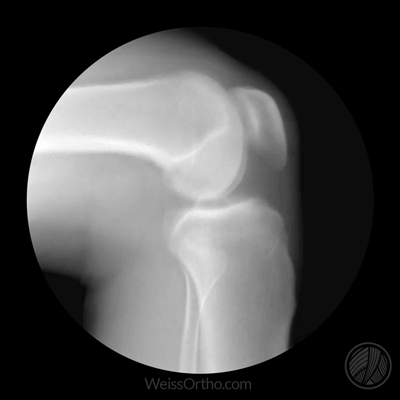

- L'objectif principal de la radiographie est de déterminer si le patient présente un rétrécissement important de l'espace articulaireLa principale raison de ce rétrécissement est que le cartilage s'est considérablement aminci et que l'espace articulaire naturel est plus étroit. En outre, nous pouvons très bien juger les articulations des personnes âgées à l'aide de radiographies.S'il y a une formation osseuse importante (ostéophytes)qui se forment spécifiquement dans telle ou telle partie du corps, les fonctions qu'elles peuvent affecter chez les personnes âgées, et lesLa formation d'ostéoïdes et le rétrécissement de l'espace articulaire sont les changements les plus classiques de l'arthrose.。

- 而L'objectif principal de l'IRM est de déterminer le degré d'usure du cartilage dans les articulations des personnes âgées, la présence de liquide dans les articulations, la quantité de liquide et l'usure du ménisque dans les articulations.Le test est souvent effectué par un médecin. Souvent, les personnes âgées dont les symptômes ne sont pas particulièrement graves et dont les déformations articulaires ne sont pas particulièrement évidentes se prêtent mieux à ce test, mais il va de soi que les personnes qui en ont la possibilité devraient subir les deux tests.

Lorsque le cartilage des articulations est usé dans une moindre mesure, le patient ne ressent rien, mais au fur et à mesure que le cartilage s'use de plus en plus sérieusement, l'étendue devient de plus en plus grande, l'épaisseur de l'usure devient de plus en plus grande, alors nos articulations dans le processus de flexion, d'extension et d'activité, la pression entre les os augmente, notre corps afin de mieux réduire la pression sur les articulations entre les os et les os, afin de mieux réduire la pression sur les articulations entre les os, le cartilage est usé de plus en plus gravement, l'épaisseur de l'usure devient de plus en plus grande.trouveront des moyens d'augmenter la taille de l'os, puis des ostéophytes commenceront à apparaître, l'hypertrophie osseuseLa naissance d'une période relativement courte ne produira aucun symptôme, mais si elle est de plus en plus importante, elle affectera de plus en plus la fonction des articulations du patient, ce qui aura pour conséquence que les patients voudront s'accroupir et ne pourront pas descendre, qu'ils voudront plier les jambes et ne pourront pas les plier en position normale, que certains patients apparaîtront également comme de sérieux obstacles au redressement, la situation ci-dessus est très courante chez les personnes âgées, nous l'appelons le "syndrome de l'accroupissement".L'arthrose, dont des études ont montré qu'elle touche 50 % des personnes âgées de plus de 65 ans.。

En général, lorsqu'une personne vieillit, la colonne vertébrale lombaire et les articulations du genou sont considérées comme l'un des organes du corps qui posent le plus souvent des problèmes. L'articulation du genou, qui se compose de l'extrémité supérieure du tibia, de l'extrémité inférieure du fémur et de la rotule, est connue comme étant l'articulation la plus complexe du corps humain, et la stabilité de cette articulation dépend des ligaments qui l'entourent pour renforcer l'articulation en raison de la minceur de la capsule articulaire.

Il est indéniable que la principale cause d'invalidité chez de nombreuses personnes d'âge moyen ou avancé est l'arthrose du genou, qui est à l'origine d'environ 85 % des arthroplasties totales du genou.